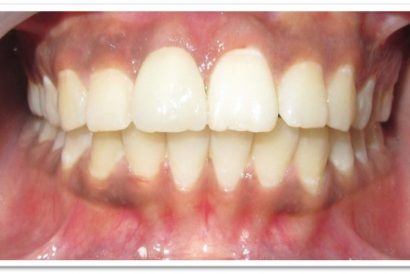

After

Patient Name:Padma Harkar

Tooth Involved : 11 12 13 21 22 23

Diagnosis : Fluorosis

Treatment : Direct Composite Veneers

Restoration: Direct Composite Using Nanohybrid composite

Stains masked using IVOCLAR EMPRESS COLOUR White And Honey.